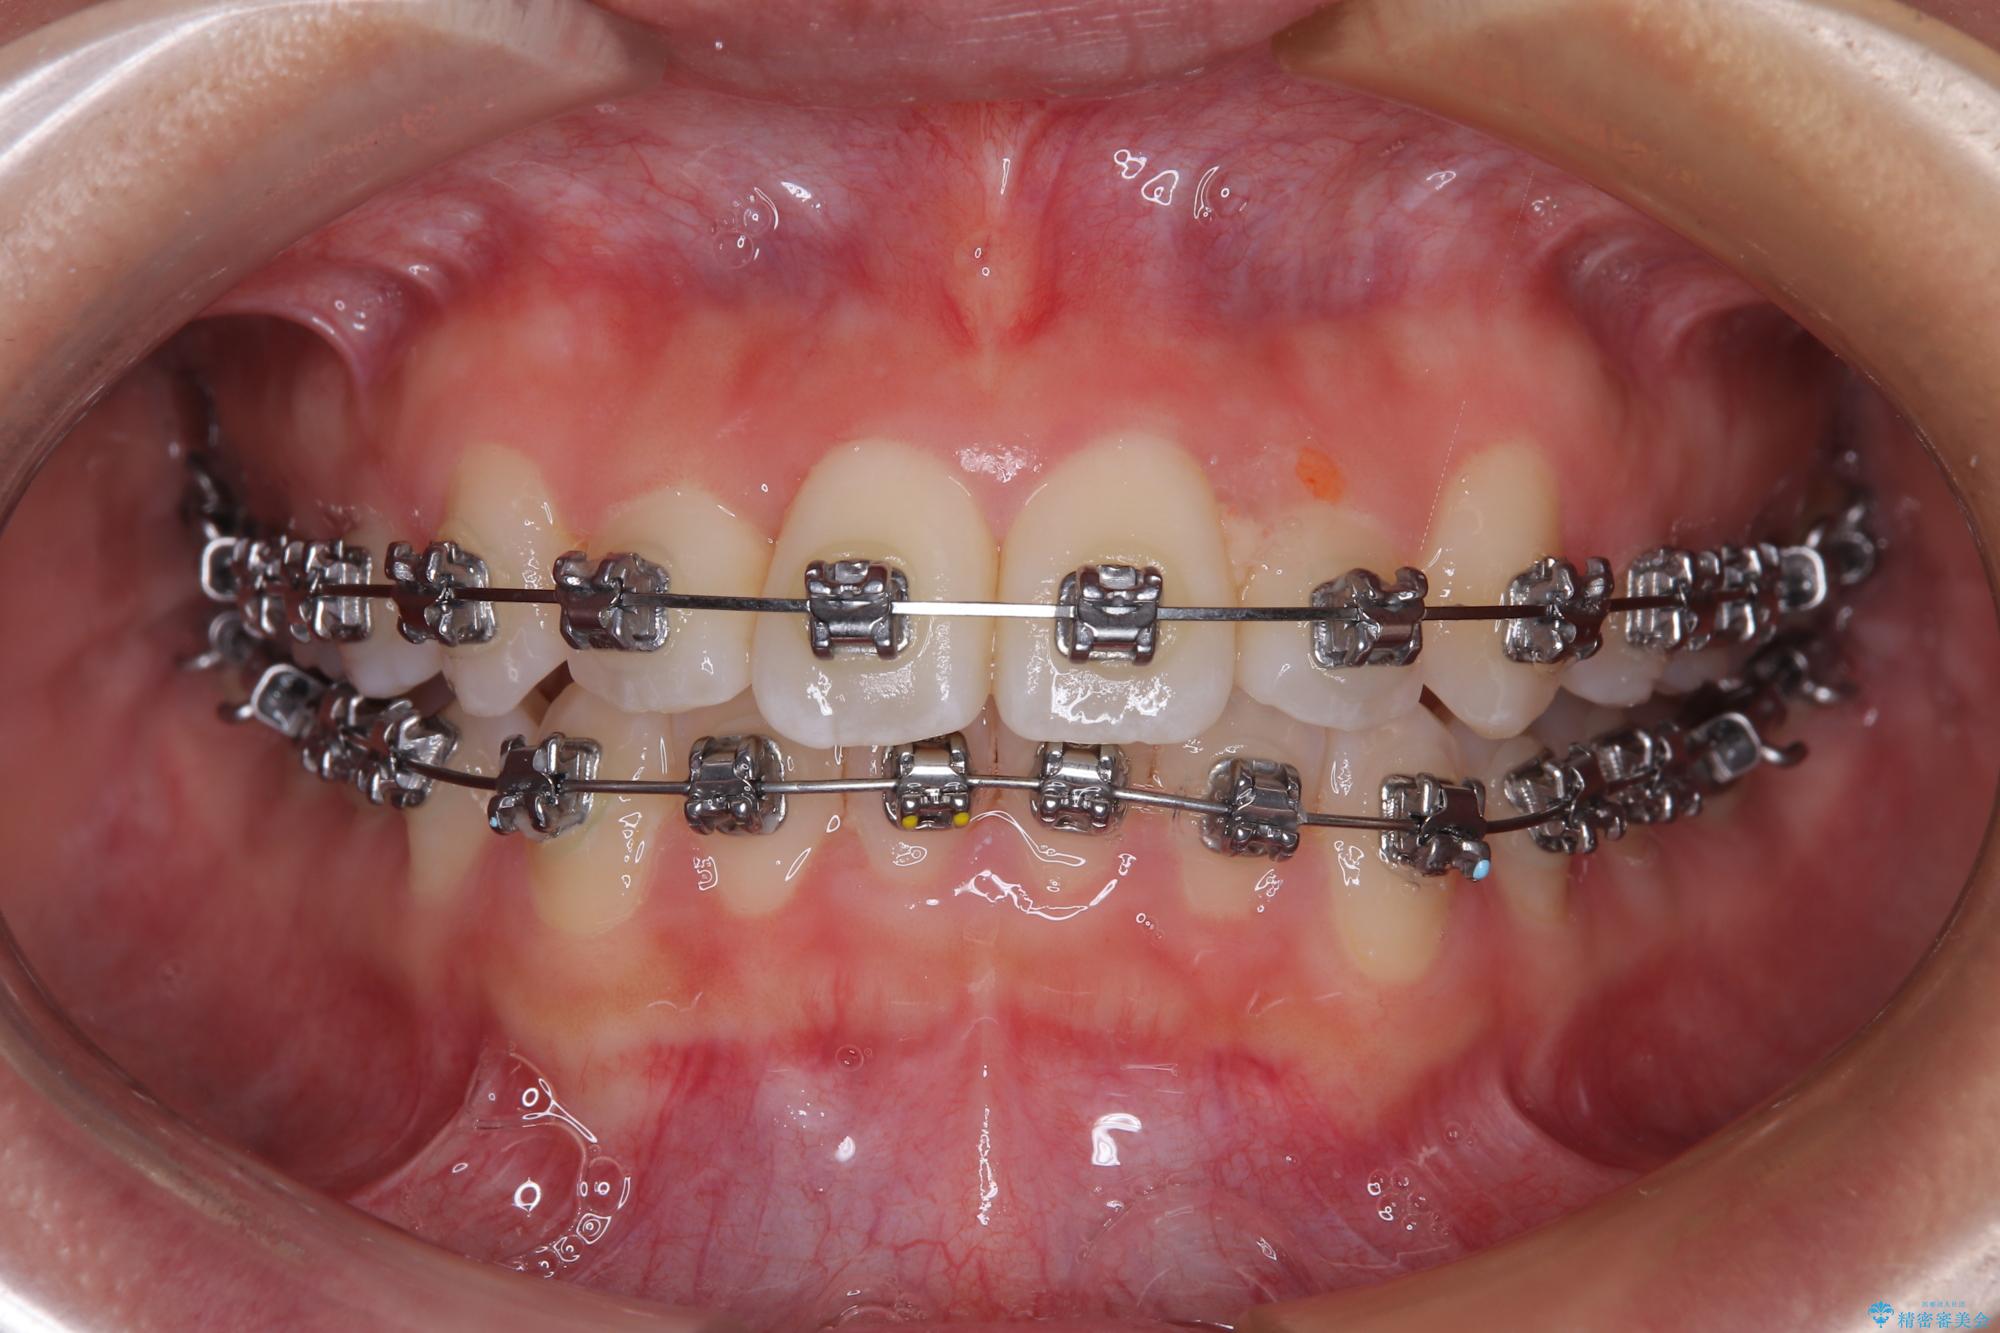

- メタルブラケット

装置の外見を気にしていましたが、短期間で治療を終えることができるだろうと伝えると、安価であるメタルブラケットを選択されました。

想定通り、1年強で綺麗に仕上げることができました。